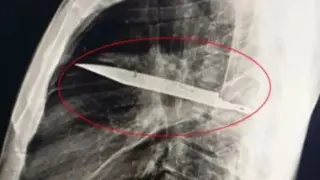

- ضبط طرفي مشاجرة بالأسلحة البيضاء في الشرقية وإحالتهم للنيابة